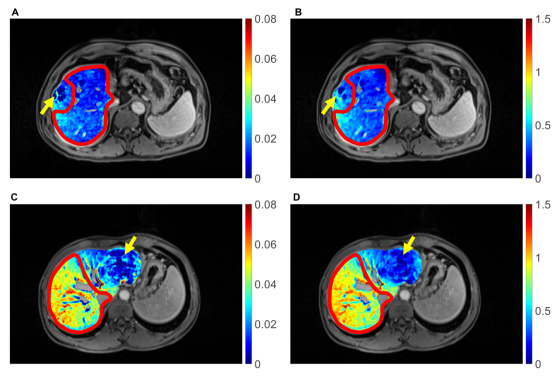

图1 肝衰患者术前Gd-EOB-DTPA肝细胞内吸收速率UR(A)、肝实质15分钟相对增强RE15(B)与非肝衰患者术前Gd-EOB-DTPA肝细胞内吸收速率UR(C)、肝实质15分钟相对增强RE15(D)的对比。两者具有相似的剩余肝脏(红色区域)体积/标准肝体积比(RLV/SLV),但剩余肝脏功能参数RFUR(ml/min)和RFRE15(ml)差异大。黄色箭头指示肝癌所在的位置。